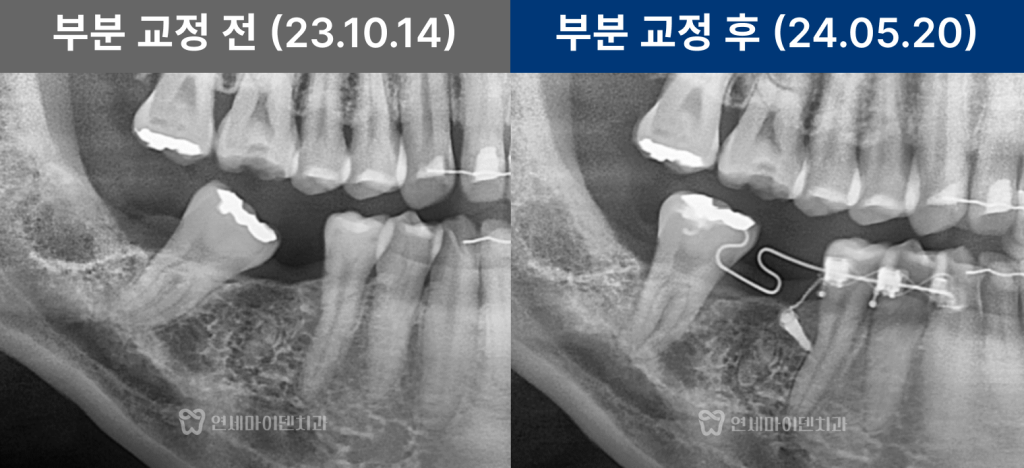

임플란트 공간이 부족했던 초기 상태

해당 환자분은 오른쪽 아래 6번 어금니를

오래전에 발치하신 분으로,

그 결과 뒤쪽의 7번 어금니와 8번 사랑니가

앞으로 기울어져 있었습니다.

이로 인해 임플란트를 식립할 공간이 부족한 상태였고,

보철만으로는 치료가 불가능했습니다.

파노라마 사진을 통해 확인한 결과,

- 6번 치아 부위의 공간이 심하게 좁아져 있었으며

- 위아래 사랑니는 모두 자라 있었고, 일부는 충치가 심했습니다.

특히 오른쪽 아래 사랑니(8번)는

앞 어금니를 제자리로 되돌리는 데 방해가 되어,

공간 확보를 위해 사랑니 발치 후

부분교정 치료를 진행하기로 하였습니다.